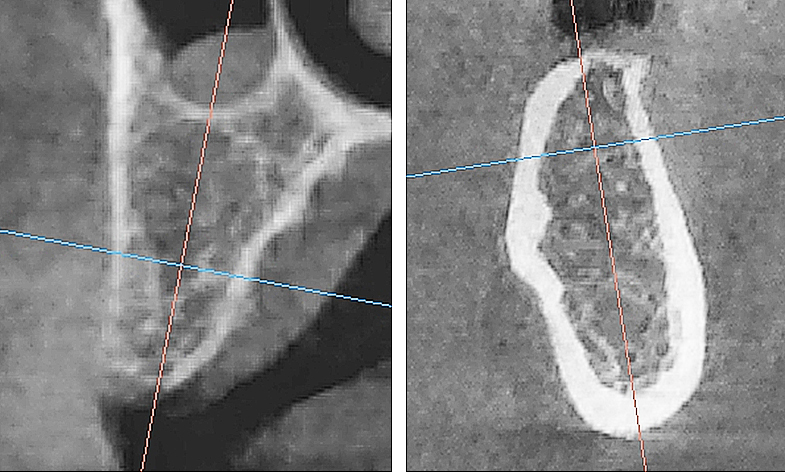

Рис. 7. Контрольная рентгенограмма локтевого отростка сразу после операции. Визуализируются 4 трепанационных отверстия, титановые пины, фиксирующие коллагеновую мембрану

После хирургического этапа проводили рентгенологический прицельный контроль в каждой области имплантации (рис. 7).